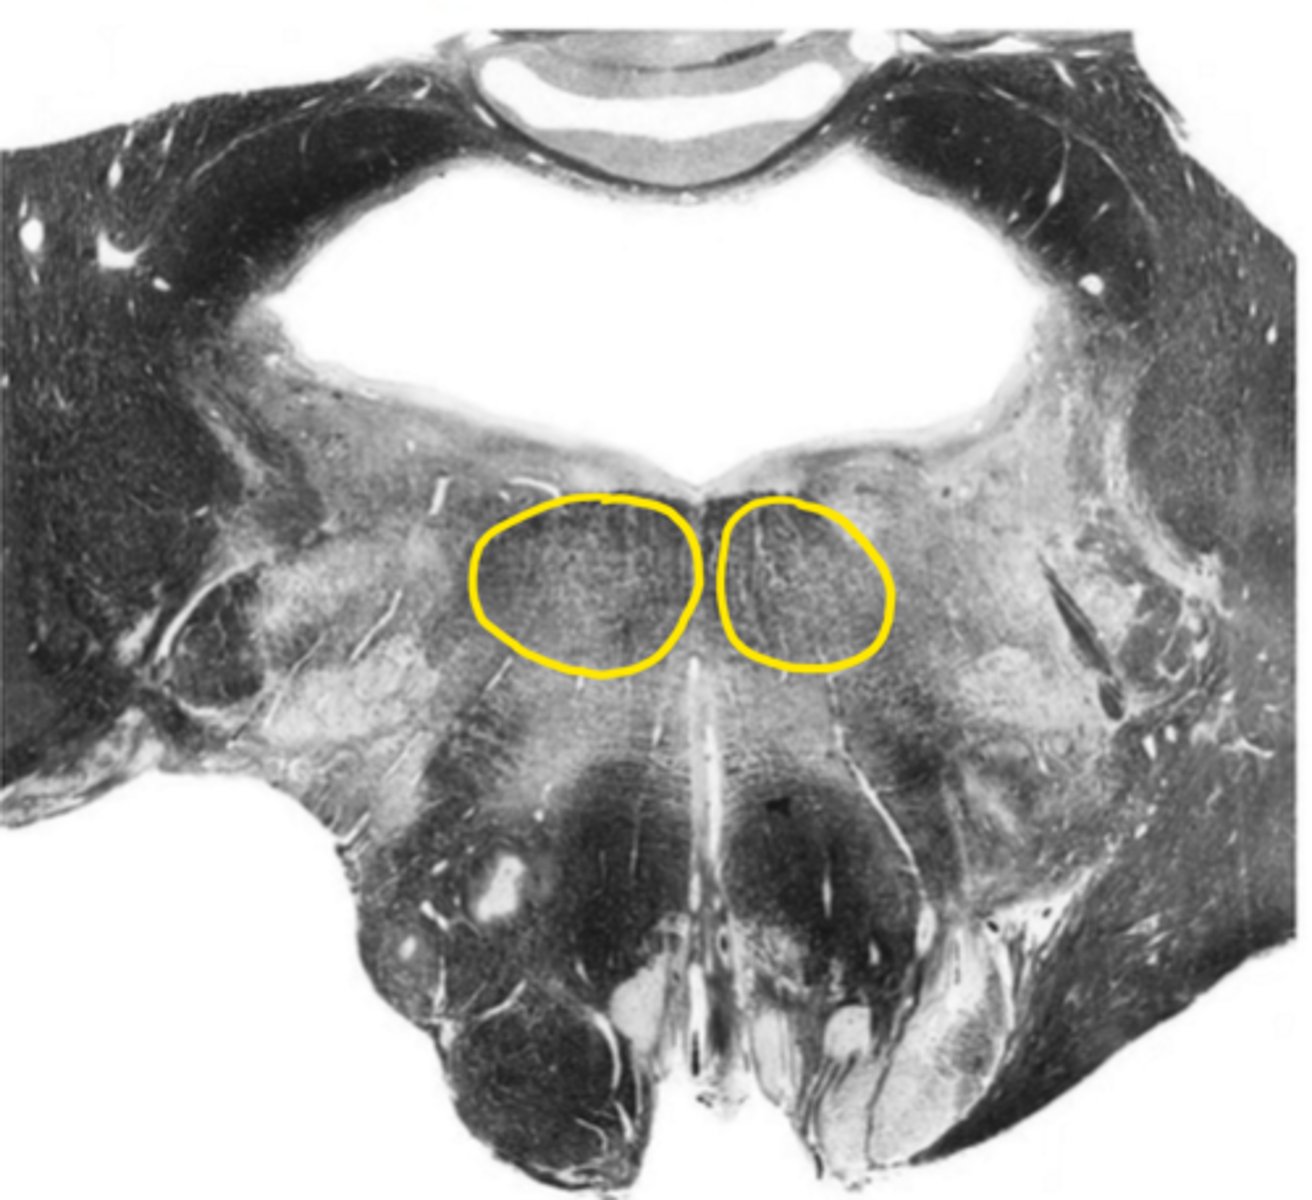

gracile nucleus

ID the nucleus

cuneate nucleus